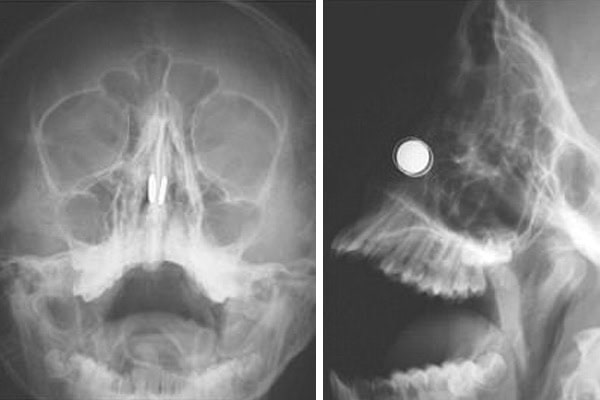

The unnamed boy, from Cyprus, was unable to remove the magnets himself after they were drawn together in the bone and cartilage that divides the nostrils. He was rushed to the’Near East University Hospital, Nicosia, while his nose was then bleeding and he was in pain. Doctors then performed a scan and found the two disc-shaped magnets located’at the same level across the nasal septum. They noted that the magnets’had began to erode at cartilage in the boy’s nose.

Previous attempts to remove the magnets were unsuccessful, so the boy was taken to the operating room under anesthesia.

Surgeons then used two additional household magnets placed on each side of the nose to slide the ones stuck in the boy’s nasal septum out of his nostrils